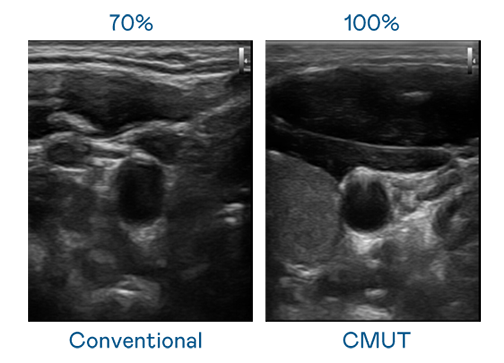

CMUT 技术是一种用电容式微机电元件来产生超音波讯号的技术。与传统 PZT 压电式技术相比,CMUT 频宽增加 30%,更宽频的超音波讯号让影像解析度大幅提升,是实现高影像品质医疗超音波扫描、促进精准医疗发展的关键技术。

超音波影像的解析度高低,首先取决于探头能发出的讯号频宽。ks凯时 CMUT 可提供高清晰的超音波讯号,提供高频宽、高灵敏度、影像纹理细节更高的超音波影像,协助医护人员缩短影像判读时间及利用精准的医疗影像进行诊断。